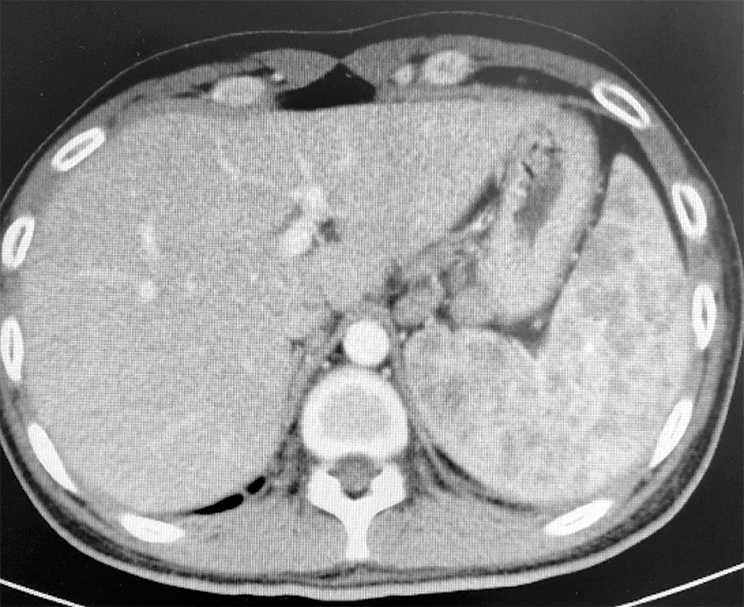

腹部CT腹膜后淋巴结肿大,脾脏多发结节病变(图3)。

图3 腹部CT示脾脏多发结节病变